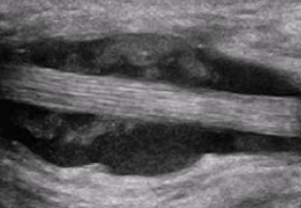

Partial or complete Achilles tendon tears

Retrocalcaneal bursitis